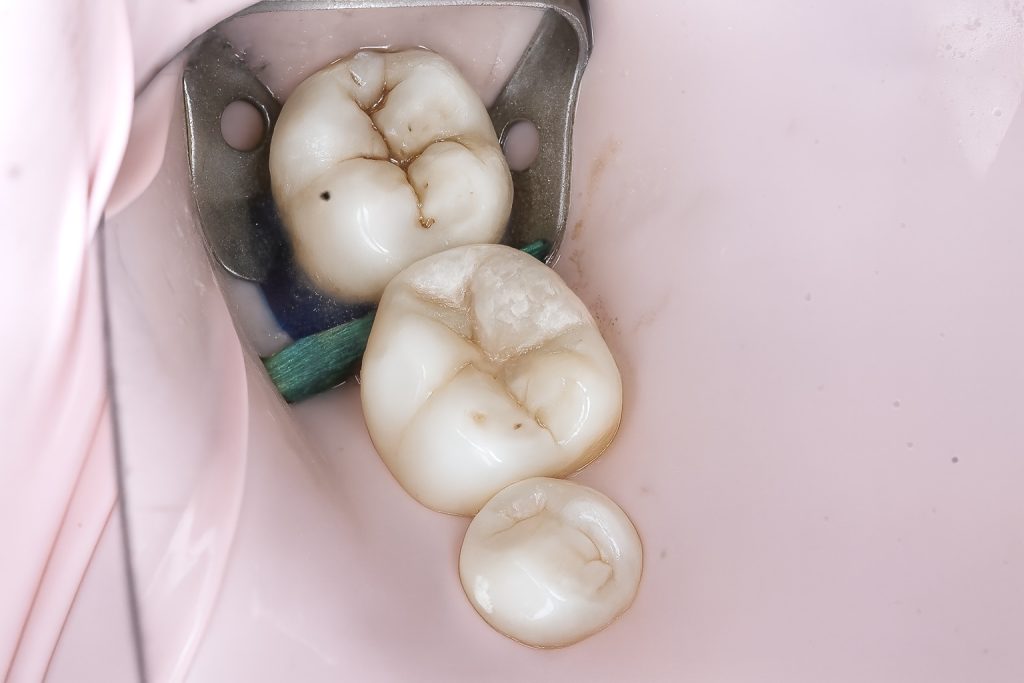

4.5 Composite Build-up

A micro-hybrid sculptable composite was placed in controlled increments:

- Initial dentin shade layer to rebuild internal anatomy

- Proximal wall built using the matrix as a guide

- Occlusal anatomy sculpted cusp-by-cusp

- Final fissure staining for natural texture

- Light cure from multiple angles for optimal polymerization

The restored proximal wall regained proper height, contour, and emergence.

5. OUTCOME

- Tight, healthy proximal contact

- Excellent emergence profile that supports papilla health

- Natural occlusal anatomy

- Smooth margins fully blended with adjacent enamel

- Zero postoperative sensitivity

- Patient reported immediate improvement in chewing comfort

The final clinical photos and radiographs reflect a clean, predictable, and biologically respectful restoration.